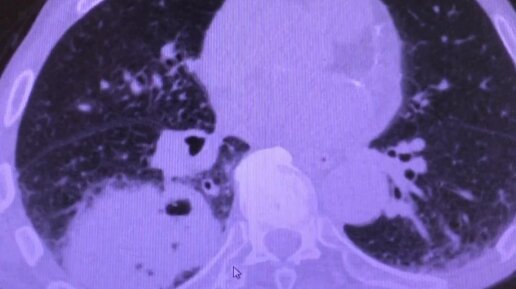

КТ грудной клетки